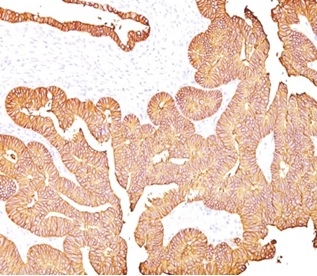

Formalin-fixed, paraffin-embedded human colon carcinoma stained with EpCAM/TROP1 antibody (323/A3) - (ECD). HIER: Tris/EDTA, pH9.0, 45min. Secondary: HRP-polymer, 30min. DAB, 5min.

Formalin-fixed, paraffin-embedded human colon stained with EpCAM/TROP1 antibody (323/A3) - (ECD). Inset: PBS instead of primary antibody; secondary only negative control.